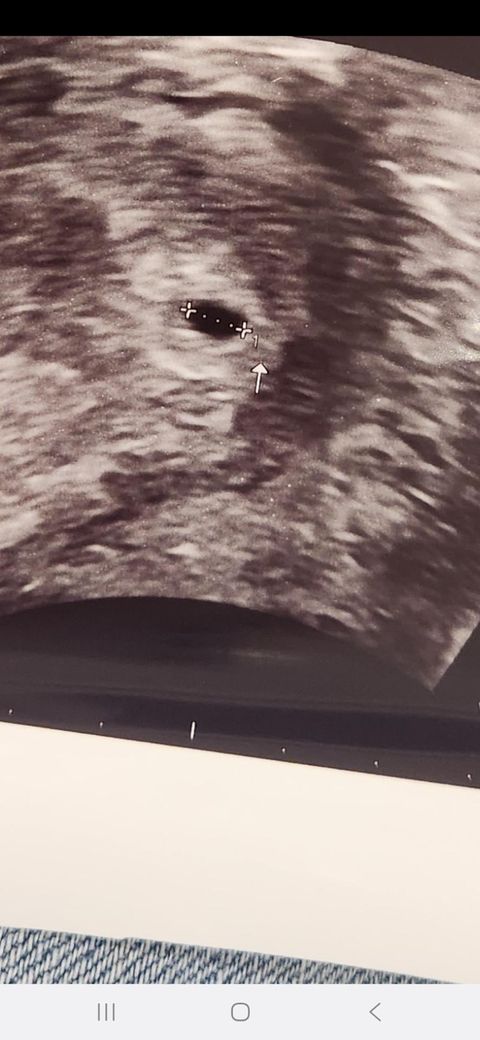

헤어진 여자친구하고 8월10일에 관계으 가졋는데 배란일이라고 하더라구요 질외사정은 햇는데 여자가 쿠퍼액으로도 임신이 가능하다고 하면서 불안했는데 20일에 임신테스트기는 안나왓구 21일이 생리날인데 안나와서 22일에 터졋다고 했는데 금요일에 갑자기 지금 사진처럼 생겻다고 하는데 어떻게 10일안에 저렇게 애기집이 생기나요?? 거짓이겟죠??? 제발 알려주세요 제애가 아닌거 ㄱ같은데 우기네요

• 1번 째 사진

아기집은 임신 4~5주경, 보통 생리 예정일 기준으로 1~2주 후, 초음파 검사를 통해 확인 할 수 있습니다.

따라서 예정일이 21일이었다면 시기적으로는 일치되진 않습니다.